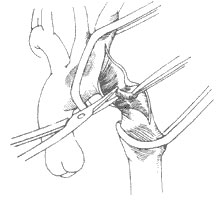

套用鎖骨下動脈瓣作主動脈成形術:嬰兒幼兒主動脈縮窄病例施行縮窄段切除術的手術死亡率較高,而且由於主動脈口徑細小,僅為成年人的50%,對端吻合術後形成的環狀疤痕組織難於隨體格成長而增大,因而術後主動脈再狹窄的併發率高。1966年Waldhausen和Nahrwold倡用鎖骨下動脈瓣修補擴大嬰幼兒主動脈縮窄,術後主動脈再狹窄的併發率顯著降低。術前準備、麻醉方法和手術切口與施行主動脈縮窄段切除術相同。進胸後游離主動脈和左鎖骨下動脈,結紮、切斷動脈導管或動脈韌帶,較大的動脈導管則需作切斷縫合術。在胸腔頂部結紮左鎖骨下動脈和椎動脈。結紮椎動脈可避免術後產生鎖骨下動脈竊血綜合徵。在左鎖骨下動脈與左頸總動脈之間放置主動脈近段血管鉗,再在縮窄段下方訪華團降主動脈血管鉗,在胸腔頂部切斷左鎖骨下動脈,然後縱向切開左鎖骨下動脈全長,切口下緣延伸及主動脈縮窄段和縮窄段下方降主動脈約1cm,切除縮窄段主動脈腔內增厚的內膜和中層組織構成的隔膜。將左鎖骨下動脈瓣向下翻轉,先用縫線1針將動脈瓣與主動脈切口下緣縫合結紮後,再將動脈瓣前、後緣與主動脈切口前、後緣作連續或間斷縫合。由於縫合線呈U形,主動脈前後壁日後生長能力未受影響,術後不至於發生再狹窄(圖4)。

先天性主動脈縮窄圖4 套用鎖骨下動脈瓣作主動脈成形術